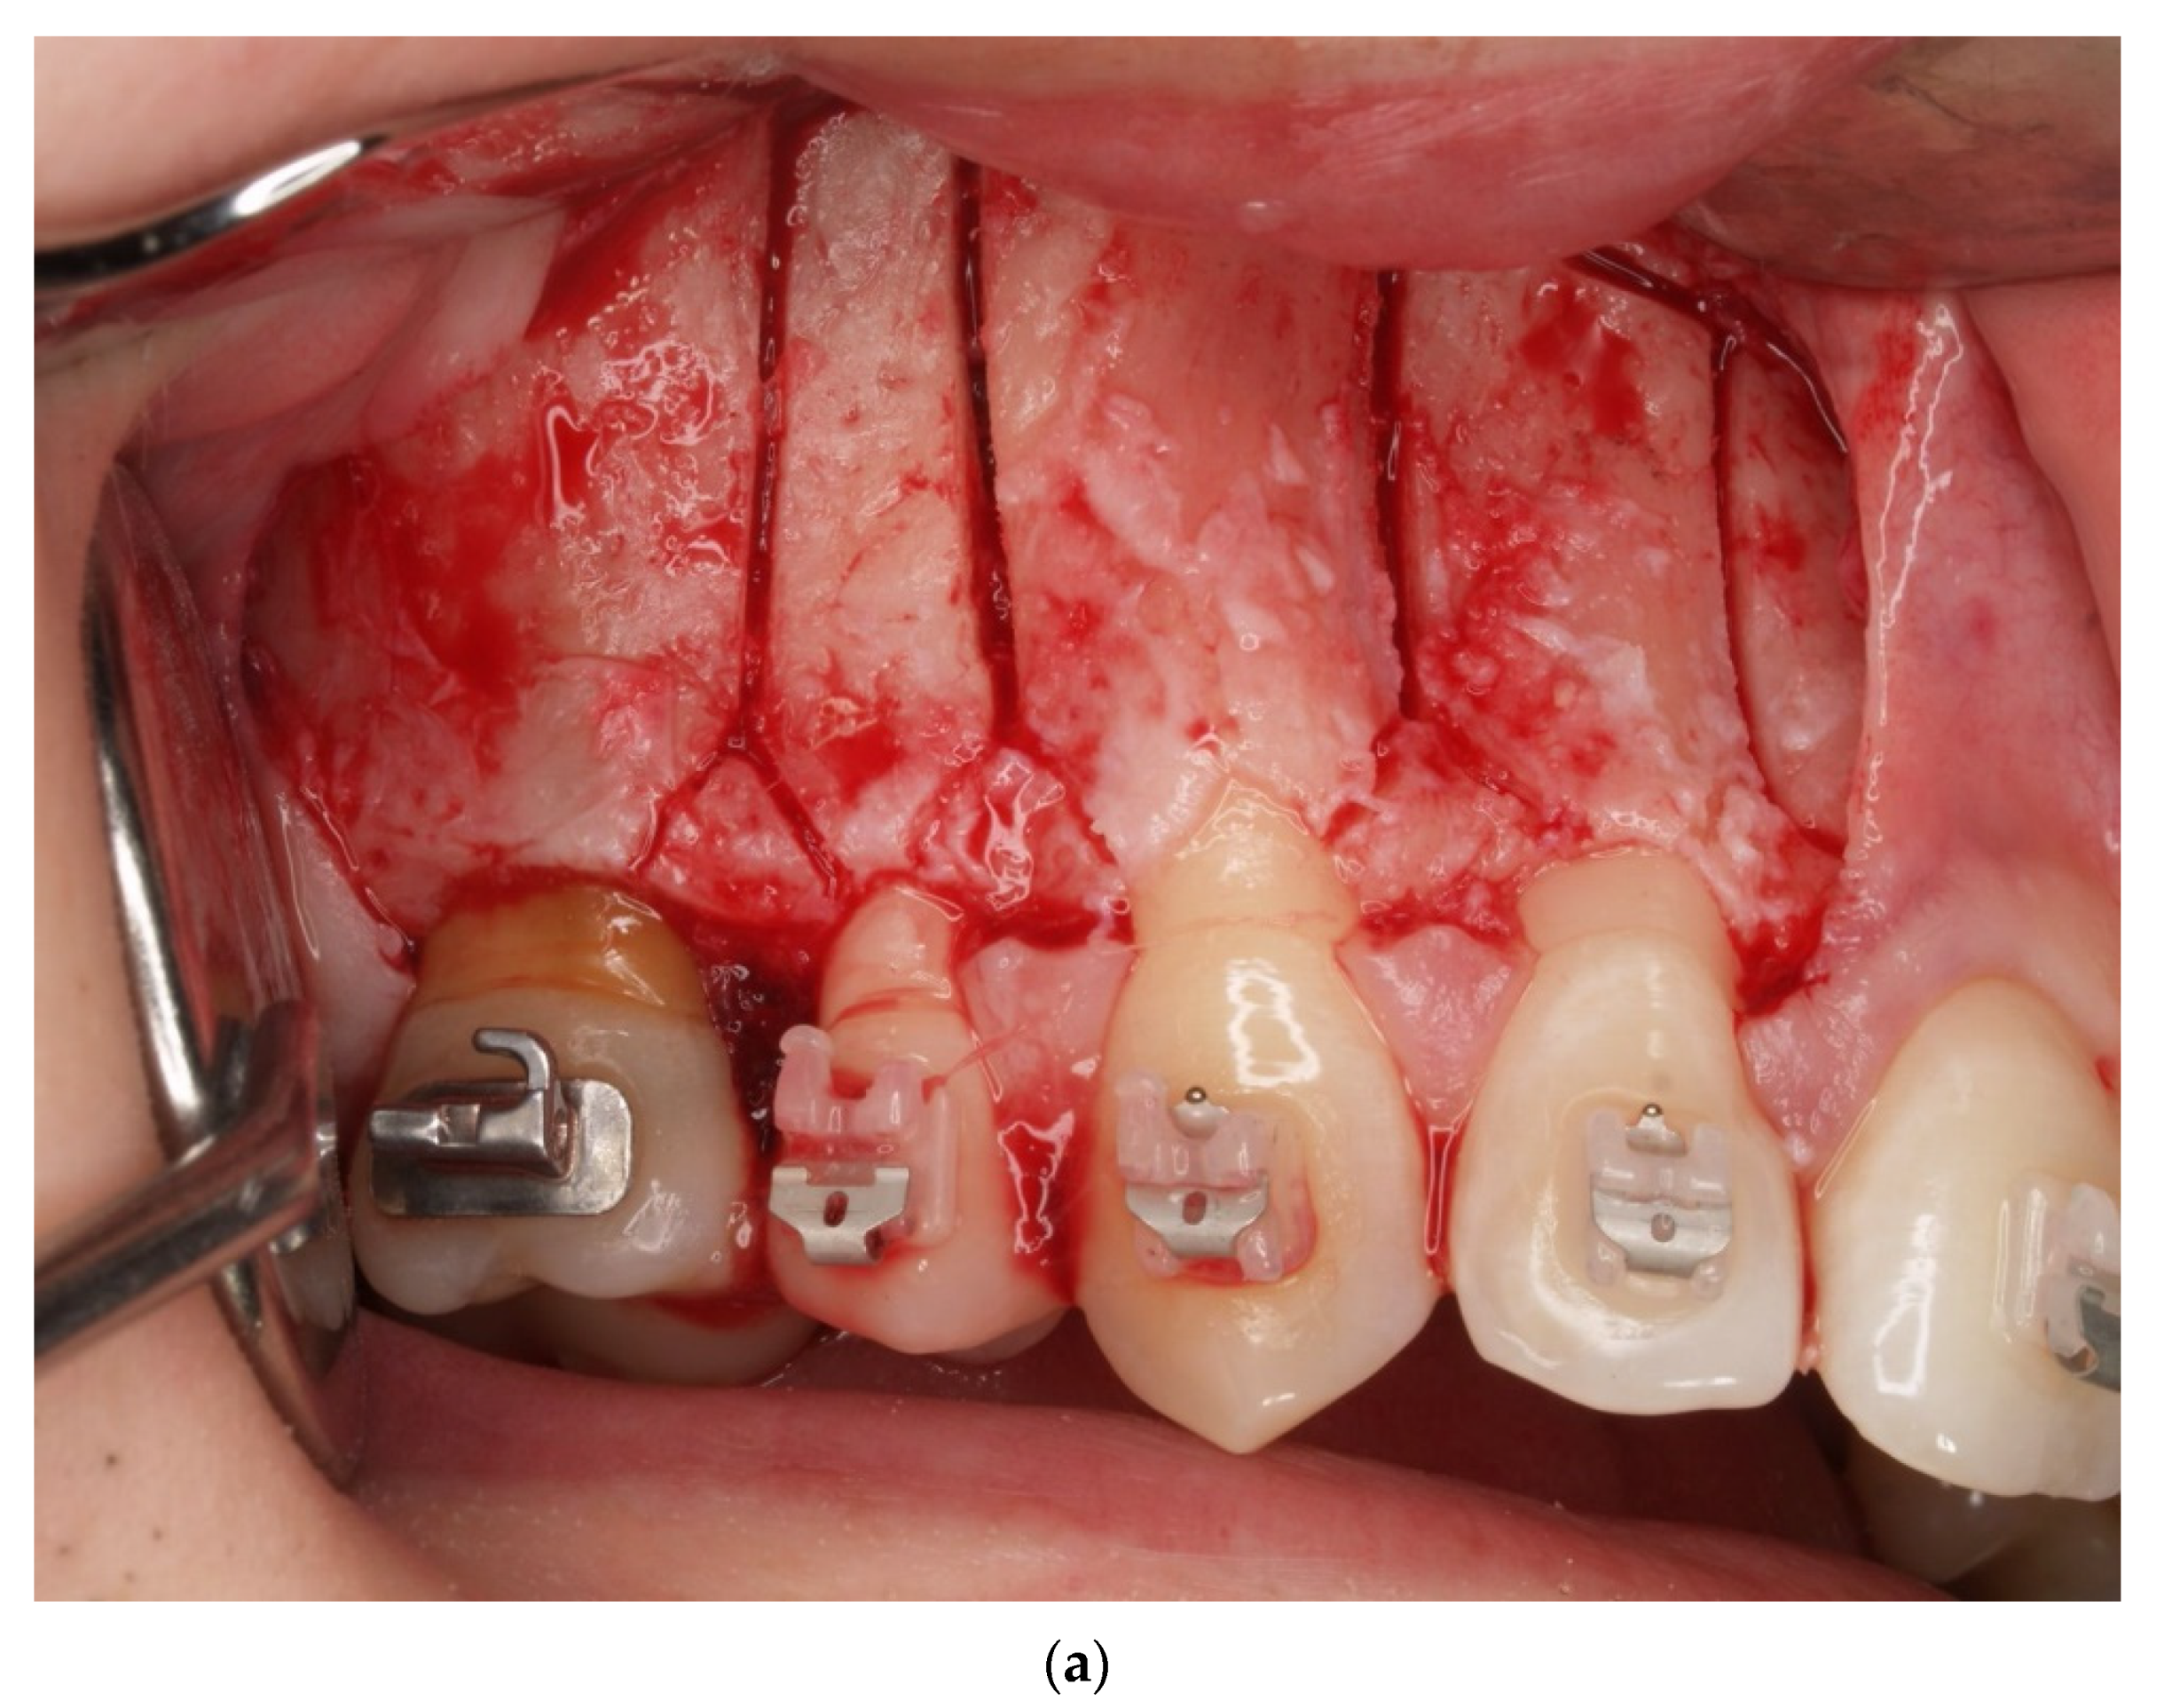

2. Materials and Methods

4. Results

- Sulewska, M.; Duraj, E.; Bugała- Musiatowicz, B.; Waszkiewicz -Sewastianik, E.; Milewski, R.; Pietruski, J.; Sajewicz, E.; Pietruska, M. Assesment of the effect of the corticotomy-Assisted orthodontic treatment on the maxillary periodontal tissue in patients with malocclusions with transverse maxillary deficiency: A case series. BMC Oral Health 2018, 18, 162. [Google Scholar] [CrossRef]